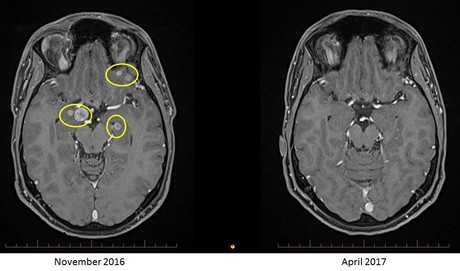

Researchers from Melanoma Institute Australia (MIA) are said to be the first to demonstrate that patients with advanced melanoma which has spread to the brain can have increased life expectancy and possibly even beat the disease.

Results from an early analysis of this trial show 79% of advanced melanoma patients with brain metastases treated with the combination immunotherapy were still alive at six months. 66% of those who got nivolumab alone were also alive after six months.

Typically, patients with active brain metastases survive only four to five months and never even used to be admitted to clinical trials because their prognosis was so dire. Australian researchers are the first to demonstrate that patients with advanced melanoma which has spread to the brain can have increased life expectancy and possibly even beat the disease.